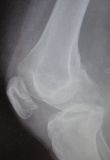

I. Before the surgery , lateral x-ray of the knee shows the chondroma (red arrow) II. Post-surgery, lateral x-ray of the knee shows that the chondroma has been removed III. Post-surgery, the photo (posterior site of the knee) is showing the specific approach that has been used for the operation.